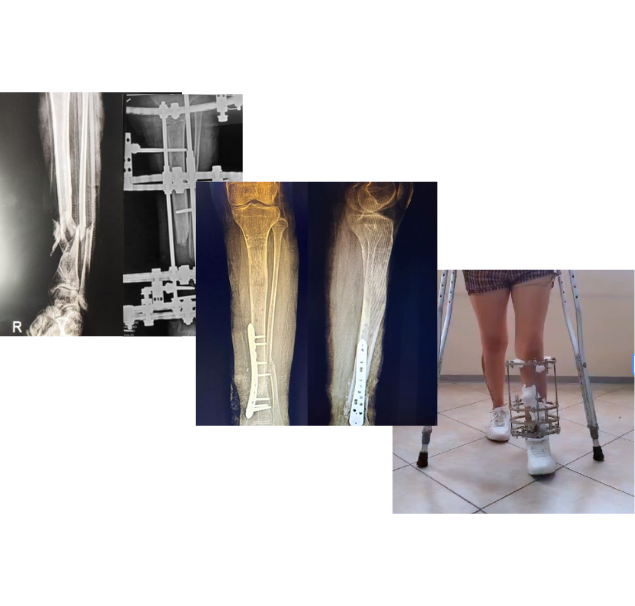

Tras un accidente de tránsito, Yessenia presentó una fractura expuesta con un defecto óseo de 10 cm en su pierna. Había recibido tratamientos previos sin éxito y su movilidad estaba en riesgo.

Con la técnica de osteogénesis por distracción y el uso de un tutor circular Ilizarov, se inició un proceso de regeneración ósea progresiva, acompañado de un seguimiento cercano.

Hoy Yessenia evoluciona favorablemente, conserva movilidad en su rodilla y tobillo, y está recuperando la independencia que pensaba perdida.